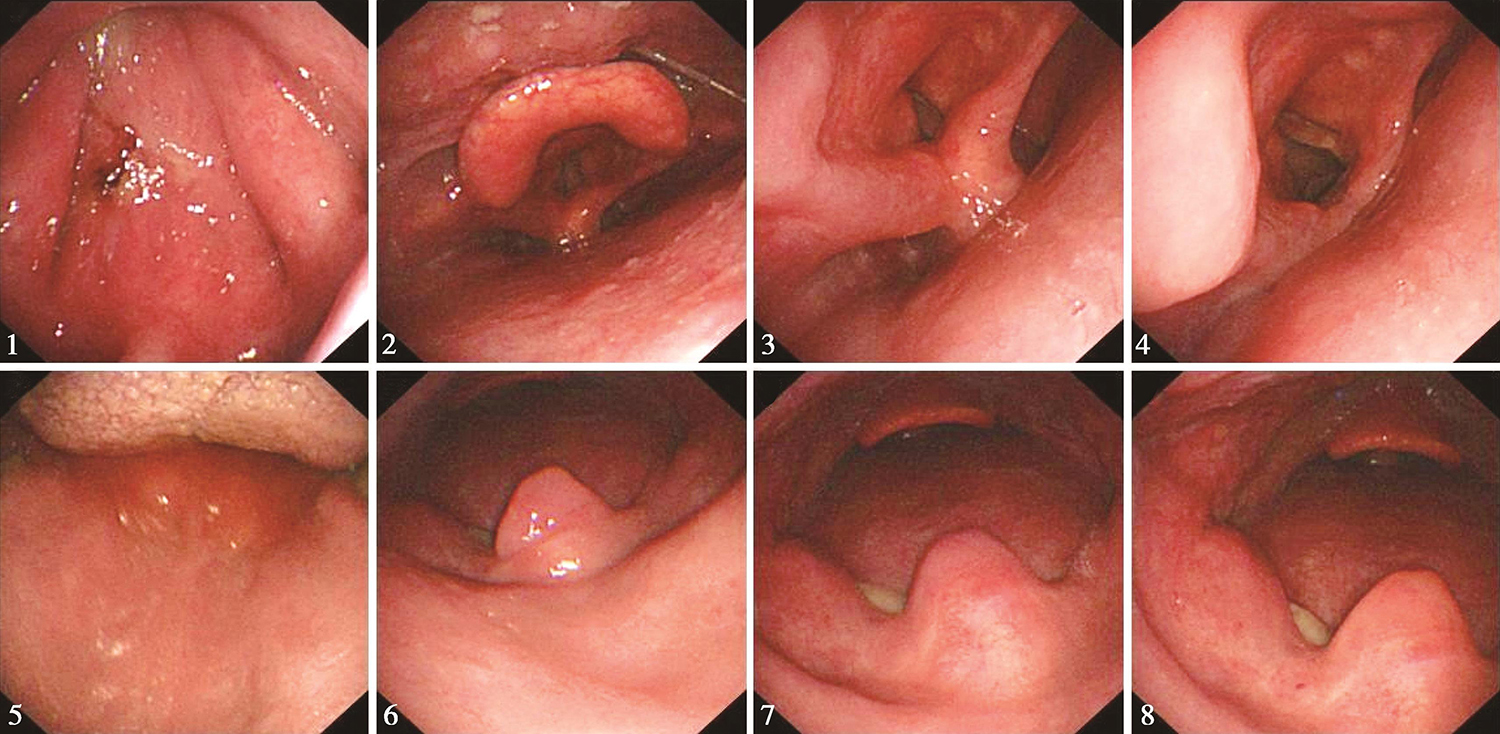

6.2016年10月20日电子胃镜检查

检查所见:

食管黏膜粗糙且碘染色后可见散在阳性灶(于距门齿约为34cm 3点位处活检1块),距门齿约为36~38cm食管至交界线可见条形糜烂灶(图5),食管胃交界线距门齿约为38cm。贲门、胃底及胃体未见明显异常,胃窦部黏膜充血、水肿、粗糙,幽门充血、水肿。所见十二指肠未见明显异常。

图5电子胃镜见黏膜粗糙且碘染色后可见散在阳性灶;食管至交界线可见条形糜烂灶

内镜诊断:

(1)食管碘染色后阳性灶,建议密切随诊,定期复查。

(2)反流性食管炎,建议对症治疗,治疗后复查。

7.2016年10月21日活检病理

(食管)鳞状上皮黏膜组织慢性炎症伴轻度不典型增生。